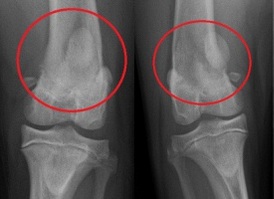

Knie     Kniescheibe ist herausgesprungen

beim Mensch     Kniescheibe ist herausgesprungen

und ist an der Seite, Röntgenfoto bei

einem Hund    Schema Knie Querschnitt

"Herausgesprungene" Kniescheibe (lat.: Platella-Luxation)

Kniescheibe ist herausgesprungen

beim Mensch

Kniescheibe ist herausgesprungen beim Mensch [4]

-- die instabile Kniescheibe [mit zu flacher Rinne] springt oft beim Sport heraus bei einer "Verdrehung des Knies" (Patella-Luxation) [web01]. Bei einer instabilen Kniescheibe reicht eine leichte Verdrehung des Knies - z.B. beim Sport - und die Kniescheibe fliegt raus [web05 (1'29''-1'36'')], oder auch bei einem Unfall kann eine instabile Kniescheibe herausspringen [web06 (20''-28''9]

-- wenn die Kniescheibe an der Unterseite oder die Rinne verformt sind und nicht mehr reibungslos gleitet, drückt die Kniescheibe von aussen gegen die Rinne, und im Extremfall kann die Kniescheibe aus der Rinne herausspringen [web04]

-- "herausgesprungene" Kniescheiben kommen in jedem Alter vor [web04], vor allem aber bei Mädchen und jungen Frauen [web02], anatomisch begünstigt mit X-Beinen und anderen Bein-Fehlstellungen [web01]